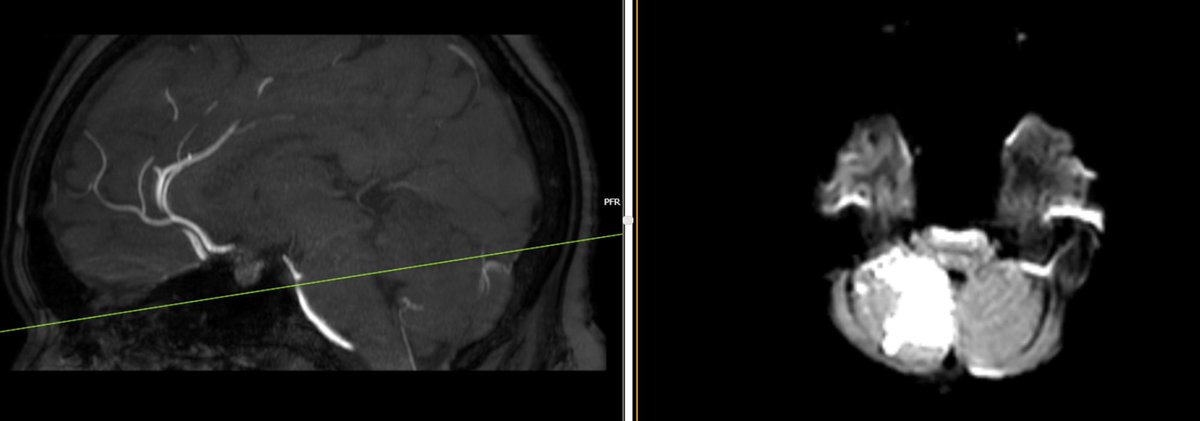

A 71-year-old man presented to us with right-sided headache after a flight. Immediately after ascent, he developed severe right eye pain and headache and lost consciousness.